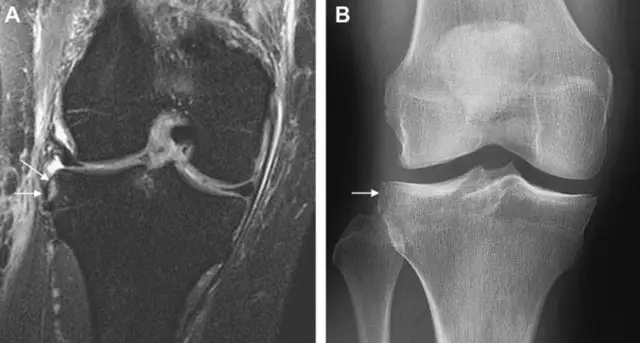

segond骨折

外髁骨擦伤(Kissing -sign)

陈旧性前交叉韧带断裂